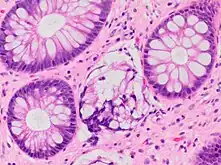

| A micrograph demonstrating cryptitis, a microscopic correlate of colitis. H&E stain. | |

An important investigation in the assessment of colitis is biopsy for histopathology. A very small piece of tissue (usually about 2mm) is removed from the bowel mucosa during endoscopy and examined under the microscope by a histopathologist. A biopsy report generally does not state the diagnosis, but should state any presence of chronic colitis, give an indication of disease activity, as well as state the presence of any epithelial damage (erosions and ulcerations).[4]

Histopathology findings generally associated with chronic colitis include:[4]

Crypt degeneration

Crypt degeneration Crypt branching and other architectural distortions

Crypt branching and other architectural distortions Paneth cell (pictured) or gastric metaplasia (only applies in the left colon and rectum)

Paneth cell (pictured) or gastric metaplasia (only applies in the left colon and rectum)

Other findings include basal plasmacytosis and mucin depletion.[4] Histopathology findings generally associated with active colitis include:[4]

Neutrophilic cryptitis (neutrophils within crypt epithelium)

Neutrophilic cryptitis (neutrophils within crypt epithelium) Crypt abscesses (luminal neutrophilic aggregates)

Crypt abscesses (luminal neutrophilic aggregates) Gland destruction

Gland destruction Ulceration (seen here as absence of epithelium, and granulation tissue with many fibroblasts)

Ulceration (seen here as absence of epithelium, and granulation tissue with many fibroblasts)